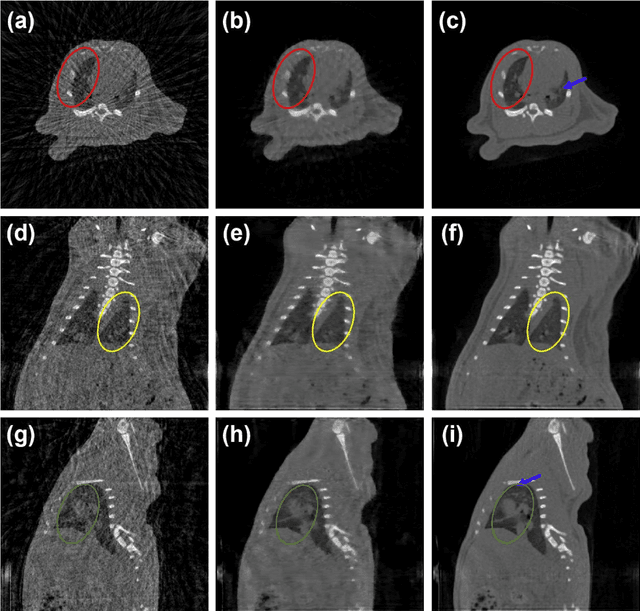

Abstract:Since the invention of modern CT systems, metal artifacts have been a persistent problem. Due to increased scattering, amplified noise, and insufficient data collection, it is more difficult to suppress metal artifacts in cone-beam CT, limiting its use in human- and robot-assisted spine surgeries where metallic guidewires and screws are commonly used. In this paper, we demonstrate that conventional image-domain segmentation-based MAR methods are unable to eliminate metal artifacts for intraoperative CBCT images with guidewires. To solve this problem, we present a fine-grained projection-domain segmentation-based MAR method termed PDS-MAR, in which metal traces are augmented and segmented in the projection domain before being inpainted using triangular interpolation. In addition, a metal reconstruction phase is proposed to restore metal areas in the image domain. The digital phantom study and real CBCT data study demonstrate that the proposed algorithm achieves significantly better artifact suppression than other comparing methods and has the potential to advance the use of intraoperative CBCT imaging in clinical spine surgeries.